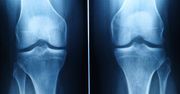

osteoporoza